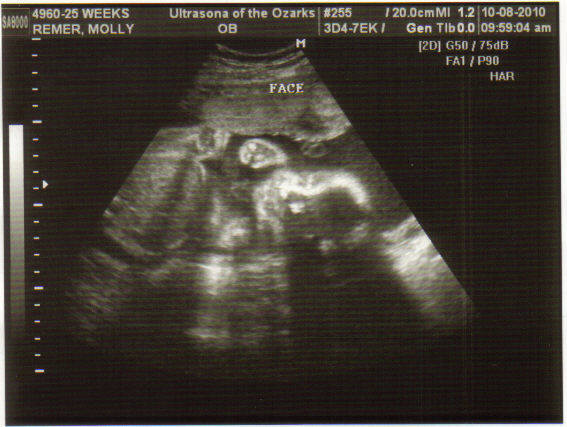

Baby's face

Here is the picture of her little face. I know u/s pictures all look the same, but I think she is cute! And, we saw her yawn đ